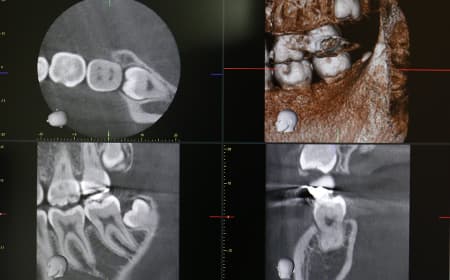

歯科用CT

歯科用CTを使うと、歯の根や顎の骨の状態、神経の位置などを立体画像で把握できます。平面画像から情報を得る従来のレントゲン写真とはくらべものにならないほど、詳細な情報を得られるのが特徴です。「三好歯科 自由が丘」では、矯正治療で使用するセファロ撮影も可能なモリタ製の歯科用CTを導入しています。